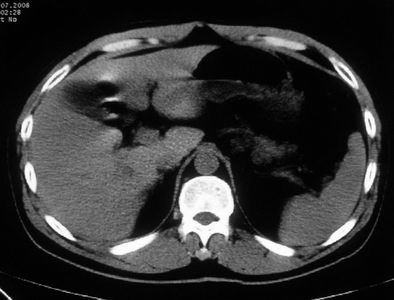

男,体查发现右肝低密度,右肾高密度结节影。高密度ct值92hu,囊肿?

肝右叶囊肿或血管瘤?右肾高密度囊肿。建议增强。

肝右叶圆形低密度灶,考虑囊肿或血管瘤,建议ct增强检查;右肾包膜下高密度圆形灶,考虑:囊肿并出血

考虑肝右叶囊肿,右肾高密度囊肿;建议行ct增强扫描检查。